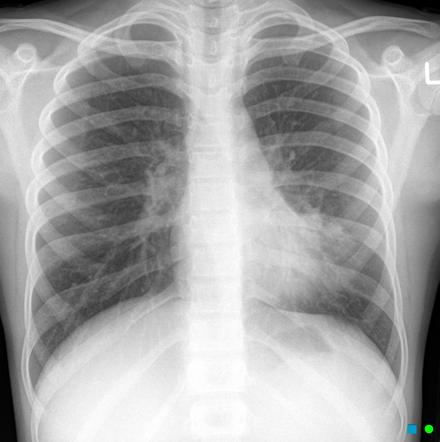

Рентген здоровых легких: примеры снимков и советы

Раздел: Сокровищница опыта